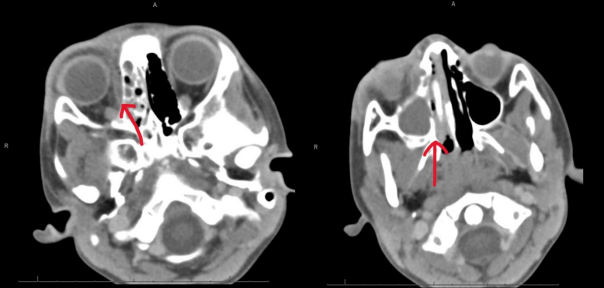

His eye swelling worsened throughout the first night of admission (Pictures 3-4). An orbital CT was obtained, which showed right orbital cellulitis with a subperiosteal abscess along the medial wall of the orbit, associated with vascular infection within the ethmoid air cells and the maxillary sinus (Pictures 5-6). Otorhinolaryngology (ENT) was consulted, who recommended endoscopic surgery in addition to starting Guaifenesin, Oxymetazoline, Fluticasone, and hypertonic saline nasal sprays. He was transferred into an intensive care step-down unit to monitor his ophthalmologic and neurologic status closely.

Pictures 5 and 6